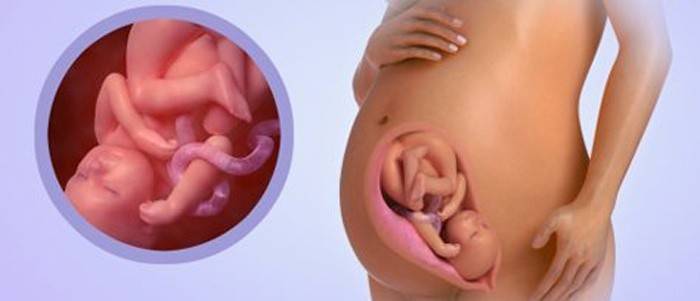

Vývoj plodu v 36. týždni: veľkosť a pohlavie

Dieťa vyrástlo na asi 47 - 48 cm, pričom hmotnosť sa môže pohybovať od 2,6 do 2,8 kg, v závislosti od individuálnych charakteristík a tempa vývoja. Dieťa má okrúhle, bacuľaté líce, nahromadené dostatok podkožného tkaniva a telo je zaoblené. To dieťaťu poskytne príležitosť na udržanie telesnej teploty po narodení. Je pre neho čoraz ťažšie pohybovať sa z dôvodu veľkosti, čoraz viac sa rozťahuje, tlačí, pohybuje hlavou a všetky jeho pohyby jasne cíti jeho matka. Aktívne saje prsty, hrá sa s pupočnou šnúrou, zívnutím, škytavkou a otvára oči. Je dôležité sledovať pohyby. Rýchlosť pohybu je najmenej desať za 12 hodín. Ak sú pohyby pomalé alebo príliš aktívne, oplatí sa ísť na prechádzku, možno má dieťa málo kyslíka.

Lebka nie je úplne osifikovaná, existujú stehy, ktoré umožňujú konfiguráciu hlavy pri pôrode a ľahšie prechádzajú cez pôrodný kanál. Je to potrebné na ochranu citlivého mozgu plodu a citlivého mozgu pred zranením. Teraz sú všetky orgány a systémy plodu takmer pripravené na narodenie a aktívne zhromažďuje silu a živiny, aby sa stretol s novým svetom. Jeho pľúca sú úplne zrelé, môže dýchať sám, hormóny sú aktívne vylučované, čo vám umožňuje regulovať metabolizmus. Zlepšuje sa nervový systém, vytvára sa stále viac nových nervových spojení a reflexov. Teraz dieťa zaujalo konečné miesto. Ak je v panvovej prezentácii, potom sa rozhodne o spôsobe doručenia